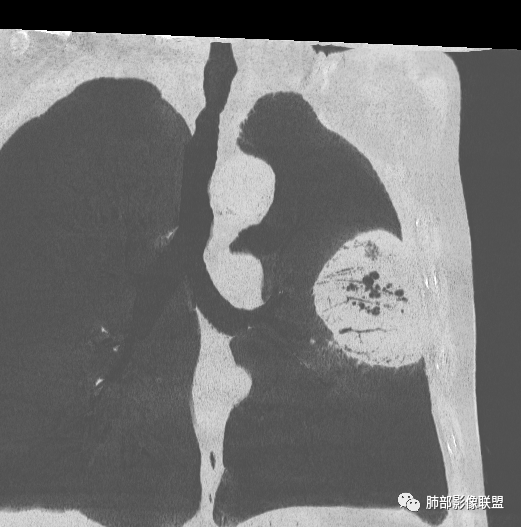

左肺上叶胸膜下肿块,宽基底与胸膜相连,跨叶裂,边缘清晰膨隆,其内支气管充气,部分扩张、僵直,无明显强化,血管造影征,考虑淋巴瘤,鉴别腺癌

左肺胸膜下巨大占位,跨叶裂,宽基底与胸膜相连,胸膜钙化,平扫密度较低,强化不明显,可见内部血管显影,支气管充气征和扩张,考虑为恶性,倾向于淋巴瘤

左侧胸腔巨大肿块,跨叶生长,临近胸膜钙化,边缘模糊,可见支气管影,定位肺内,增强后轻度强化,边缘见血管影,考虑淋巴瘤,鉴别肉瘤

左肺紧贴胸膜巨大肿块,跨叶裂生长,密度均匀,边缘清晰,内支气管略扩张,增强见血管影,强化不明显,胸膜栽赃,钙化,考虑淋巴瘤。

大肿块,边缘光滑,深分叶

部分类似于脐凹征

大肿块、表面光滑但深分叶,肺门侧支气管堵塞

1)部位:周围型或中央型软组织肿块,以周围型为多见,且肿瘤多位于肺上叶。如本例:该肿瘤位于左肺上叶。

3)肿块边界和边缘:多较清楚,呈圆形、类圆形,且由于肿块生长速度不均匀,可见分叶,毛刺少见。有报道肿块周围毛玻璃影是多形性癌特征表现。